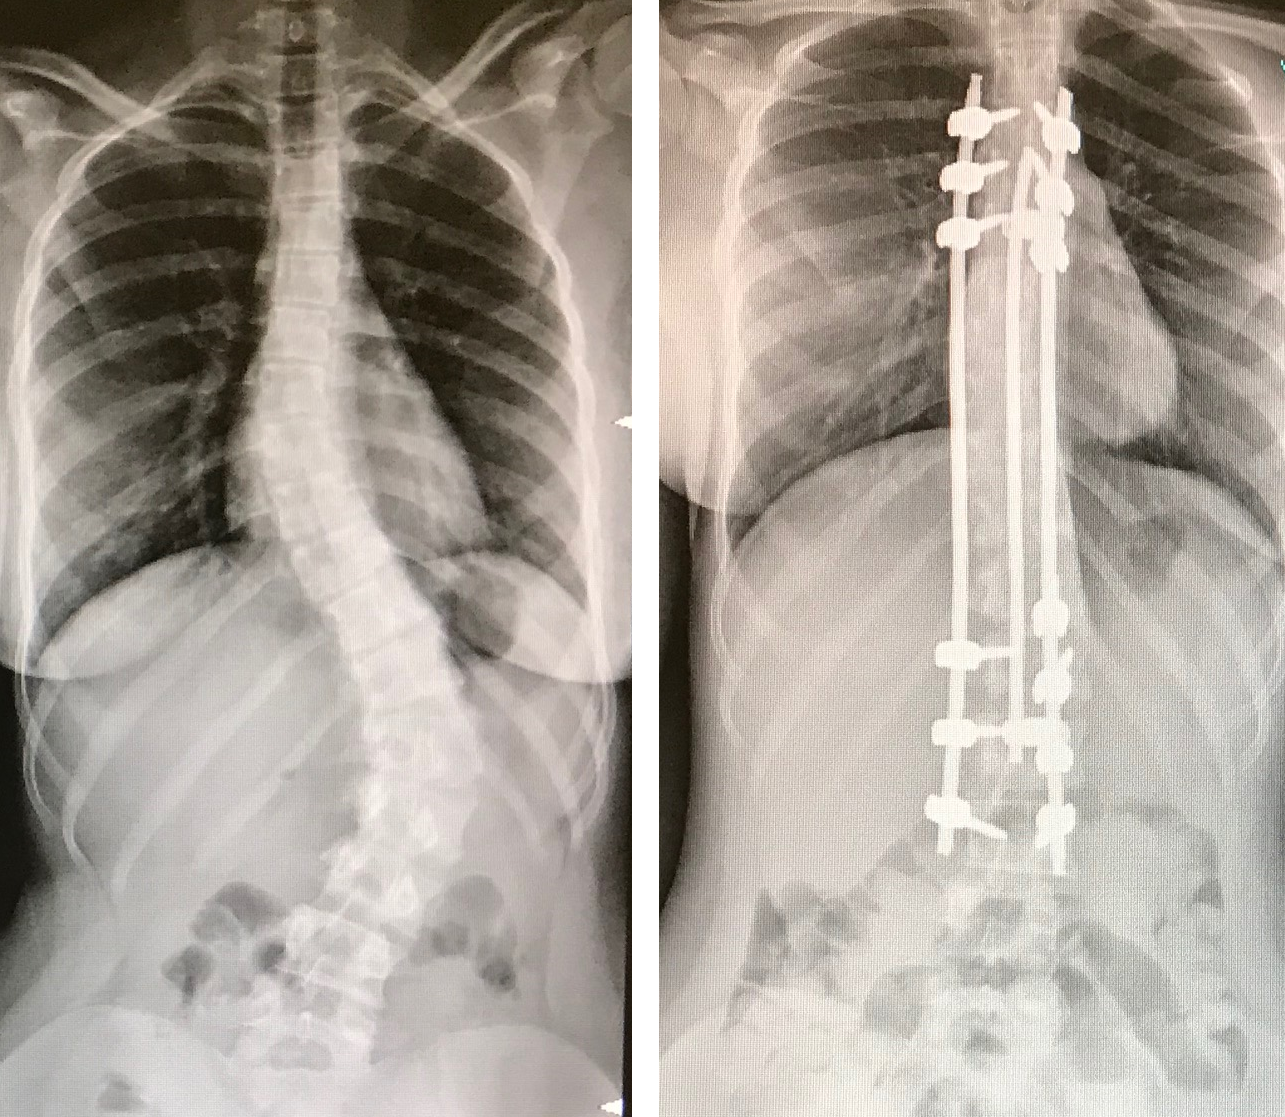

Le tecniche di correzione chirurgica della scoliosi per via posteriore si basano sull'applicazione di viti a livello delle vertebre coinvolte nella deformità e sull'uso di barre che, raccordandosi alle viti stesse, permettono la correzione della curva scoliotica mediante manovre di traslazione e di derotazione. Tali tecniche, che prevedono l’esposizione di tutto il segmento vertebrale coinvolto dalla deformità, permettono di ottenere una correzione immediatamente stabile per cui non è più necessario nella fase post-operatoria l'uso di busti. L'ampia esposizione del rachide di questi giovani pazienti determina significative perdite ematiche, uso di analgesici maggiori per diversi giorni, rischi infettivi e necessità di ricovero in terapia intensiva post-operatoria per le successive 24-48 ore e dimissione dopo 8-10 giorni senza alcuna contenzione ortesica.

Nella nostra divisione ormai da circa 3 anni eseguiamo tale intervento mediante una tecnica innovativa che prevede l'esposizione di piccoli segmenti della curva e non di tutta la deformità. La tecnica, largamente utilizzata in curve scoliotiche lombari o toracolombari con buona riducibilità nei test in bending pre-operatori, prevede di eseguire piccole incisioni cutanee (4-5 cm) a livello di 2 o 3 zone "strategiche della deformità", attraverso le quali si applicano le viti e si eseguono le osteotomie che permettono sia la fusione successiva che la correzione. Successivamente attraverso una tecnica, da noi sviluppata, si procede all'inserimento della barra sottofasciale raccordando le zone precedentemente strumentate eseguendo le manovre di correzione.

Le peculiarità di questa tecnica sono la riduzione dei tempi chirurgici di circa il 25%, la riduzione delle perdite ematiche di circa il 65%, la non necessità di ricovero in terapia intensiva bensì la sola osservazione per poche ore (da 3 a 5) in una "recovery room" situata nel blocco operatorio stesso e il successivo trasferimento in reparto di degenza ordinaria. Il giorno successivo i pazienti cominciano la fisioterapia, la rimozione del drenaggio e la deambulazione autonoma con dimissione al proprio domicilio in media dopo 4 giorni. Altri elementi peculiari di tale tecnica chirurgica sono la netta riduzione di infezioni post-operatorie e l'assenza di trasfusioni ematiche.